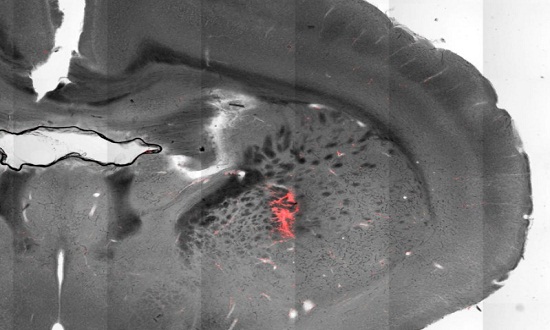

Manyetotermal uyarıda, ısıya duyarlı iyon kanallarıyla çevreli nöronları uyarmak için manyetik nanopartiküller kullanılır. Nanopartiküller bir dış manyetik alan tarafından ısıtıldığında, beyin hücreleri patlar ve böylece kanalların açılmasına neden olur.

Pralle’nin ekibi fareler üzerinde, belirli motor fonksiyonlarını tetiklemek için beynin 3 farklı bölgesini harekete geçirmeyi başardı.

Striyatumdaki hücrelerin uyarılması hayvanların etrafında dönmesine neden olurken, motor korteksindeki hücrelerin uyarılması koşma eylemini tetikledi. Bilim insanları, beynin daha derin bir bölgesini harekete geçirdiğinde ise fareler donuk halde kaldılar ve kol-bacaklarını hareket ettiremediler.

Pralle: ‘’Yöntemimizi kullanarak yaklaşık bir insan saçı genişliğinde, 100 mikrometrelik bir alanı yani çok küçük bir hücre grubunu hedef alabiliriz’’ dedi.

Manyetotermal uyarı araştırmacıların, beynin içindeki bireysel nöronları harekete geçirmek için ısıtılmış, manyetik nanopartikülleri kullanmasını sağlar.

İşleyişi: İlk olarak, bilim insanları genetik mühendisliğini kullanarak hedef nöronlara belirli bir DNA zinciri yerleştirir ve bu da bu hücrelerin ısıl etkin iyon kanalları üretmesini sağlar. Daha sonra, araştırmacılar beynin aynı bölgesine özel olarak yapılmış manyetik nanopartikülleri enjekte ederler. Bu nanopartiküller, hedef nöronların yüzeyine tutunarak soğan kabuğuna benzeyen ince bir tabaka oluştururlar.

Beyne alternatif bir manyetik alan uygulandığında, nanopartiküllerin manyetiği hızla ters döner ve hedef hücreleri ısıtan ısıyı üretmesine neden olur. Bu da ısıya duyarlı iyon kanallarının açılmasına ve nöronların ateşlenmesine yol açar.